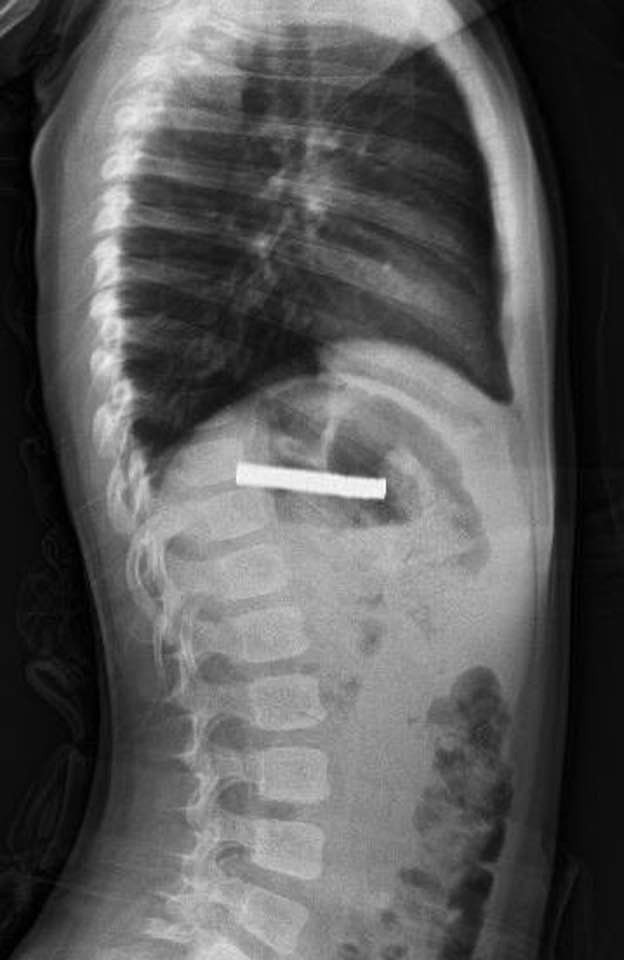

Elazığ’da 3 yaşındaki bir çocuğun yuttuğu 19 mıknatıs, Fırat Üniversitesi Hastanesinde başarılı bir operasyon ile çıkartıldı. Erzurum’da bir çocuk evde bulunan 19 tane mıknatısı yuttu. Çocuğun rahatsızlanması sonucu durumu öğrenen aile hastaneye başvurdu. Daha sonra çocuk Elazığ’a sevk edildi. Fırat Üniversitesi Çocuk Gastroenteroloji Hepatoloji ve Beslenme Bilim Dalı Başkanı Prof. Dr. Yaşar Doğan, çocuk hastanın yemek borusuna yapışmış 19 mıknatısı endoskopik yöntemle çıkardı.

Mıknatıslar uzun süre yemek borusunda takılı kaldığı için yemek borusu ve mide girişinde zedelenmeler olurken, çocuğun sağlık durumunun iyi olduğu ve taburcu edildiği öğrenildi.